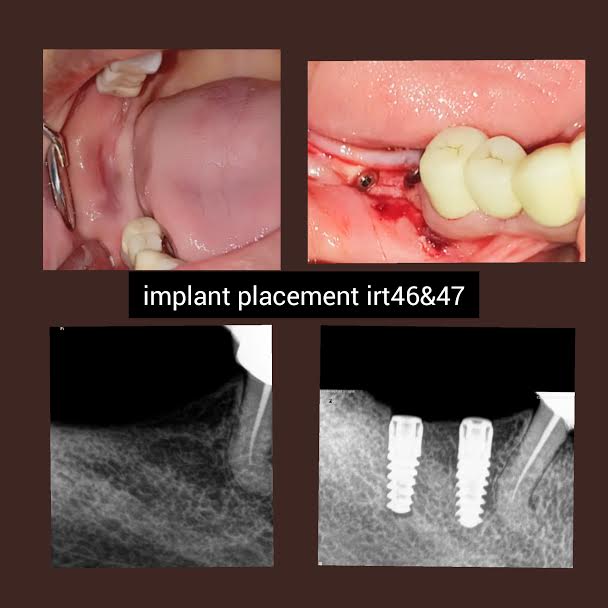

Home / Treatment Photos